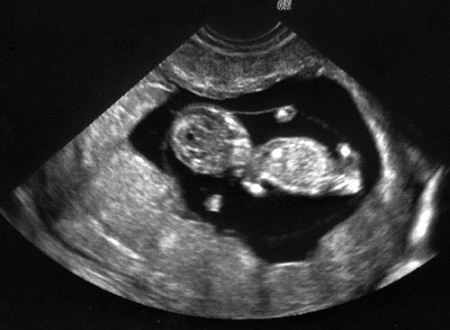

La campaña de 40 días por la vida, en EEUU, ha compartido la historia de una joven madre que en el mes de diciembre intentó abortar a su bebé tomando la píldora abortiva RU-486, estando embarazada de cuatro semanas (en la foto). Después de un test de embarazo, y viendo que aún daba un débil positivo, en enero, asesorada por una clínica abortista, tomo una segunda píldora abortiva. Después de esto, creyó haber terminado con su embrazo, ya que los test daban negativos. A pesar de ello, el día 21 de febrero, sintiéndose aún embarazada, acudió a un autobús provida aparcado frente a un abortorio. Allí le realizaron una ecografía que demostró que el embarazo proseguía y que se encontraba ya en la semana catorce. El pequeño ha tenido suerte. A pesar de que su madre afirma que fue concebido en una violación, ella ha decidido no abortar. EligeLaVida.-